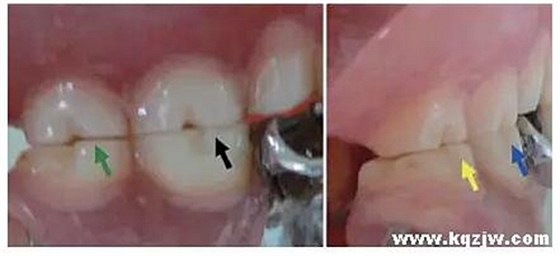

這種咬合接觸的結(jié)果是局部的咬合力集中在凸點(diǎn)接觸的位置,不能被有效分散,可造成受力部位牙體、牙周組織的應(yīng)力集中。最常見的表現(xiàn)是后牙頰舌向呈對(duì)刃關(guān)系,另外還常見于不完全遠(yuǎn)中關(guān)系或不完全近中關(guān)系的情況,此時(shí)從近遠(yuǎn)中方向來看,上下后牙牙尖之間凸凸相對(duì)(圖3)。

圖3 后牙凸凸接觸關(guān)系